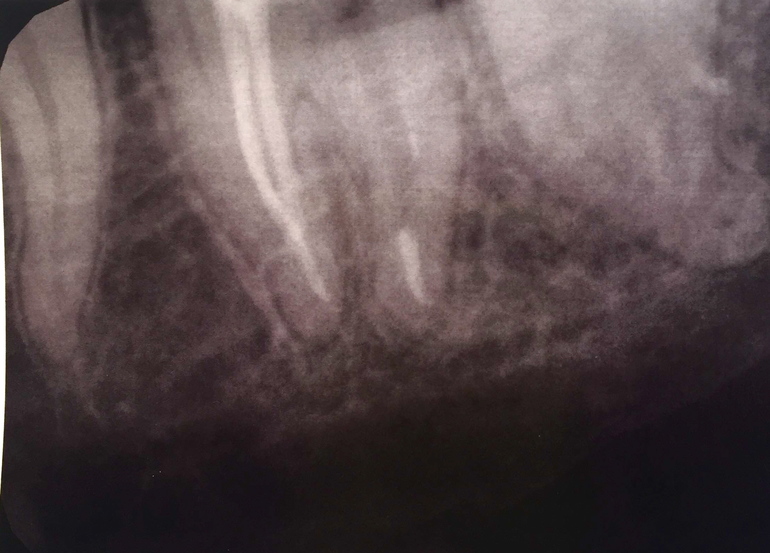

Ночью не выдержала, нашла радиовизиограф, сделала снимок.